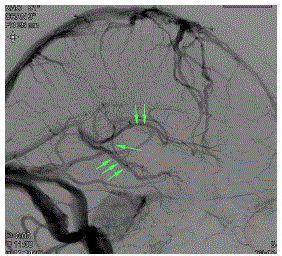

Na imagem abaixo, observamos a fase venosa de uma injeção na artéria carótida interna direita. Assinale a que estruturas venosas correspondem, respectivamente, a seta simples, as setas duplas e as setas triplas.